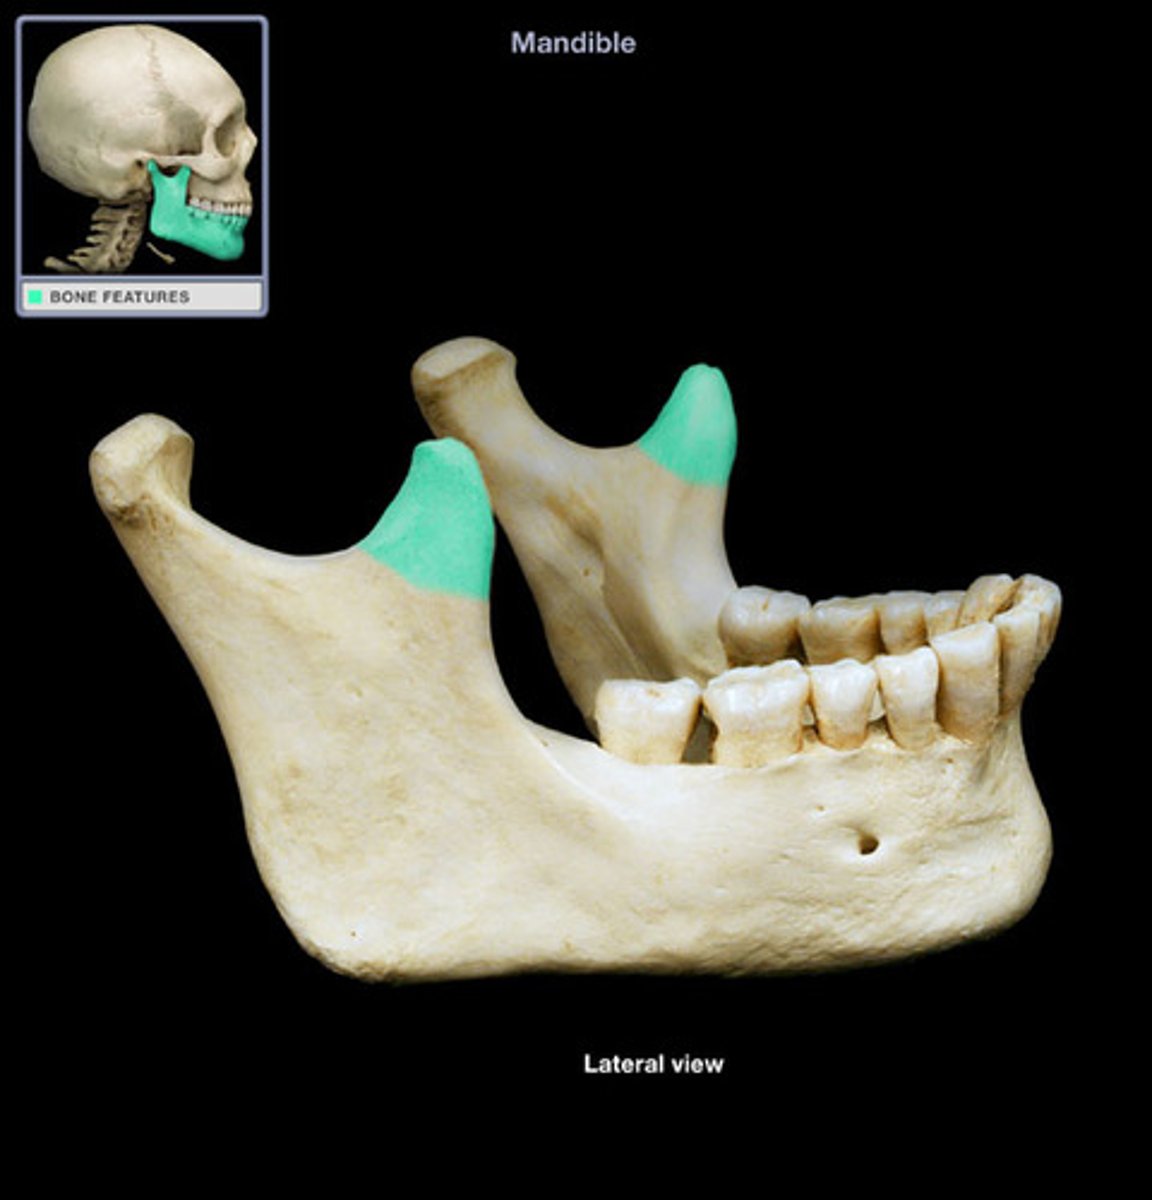

coronoid process ( anterior)

what is this

condyloid process ( posterior)

- makes up TMJ